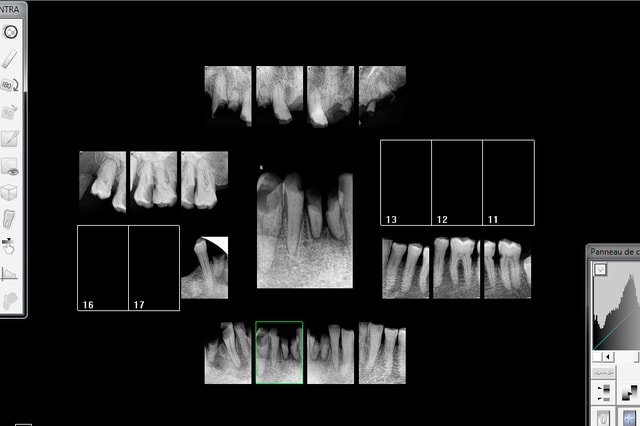

As-tu, Pluton, une pano pré-op à nous montrer qu'on se rende mieux compte de la situation initiale et as-tu objectivé la précision d'adaptation par friction en prenant quelques clichés rétroalvéoaires de contrôle ?

pano initiale et planche 3D montrant qu'en fait les molaires ne tenaient quasi plus que par les racines palatines...

pour la très grande précision d'emblée, Posit a répondu, nous sommes quelques praticiens à poser ainsi...

seules vraies difficultés: avoir parfaitement compris le système du guide Positdental et connaître/maîtriser parfaitement son système implantaire...